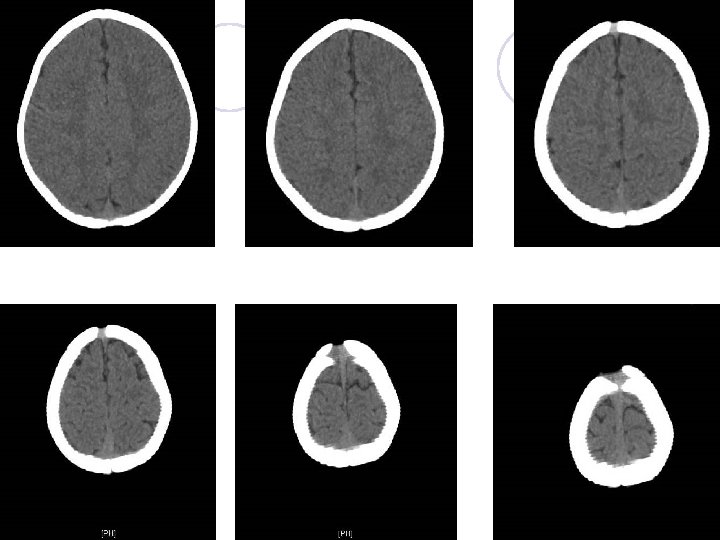

EEG (sleep) report l No evidence of cortical dysfunction. l Few focal epileptiform activity over left frontocentral areas, and rarely over left middle temporal area. Brain echo l Left subependymal cyst l No midline shift. No ventricular dilatation

Final diagnosis l Infantile seizure l Left subependymal cyst